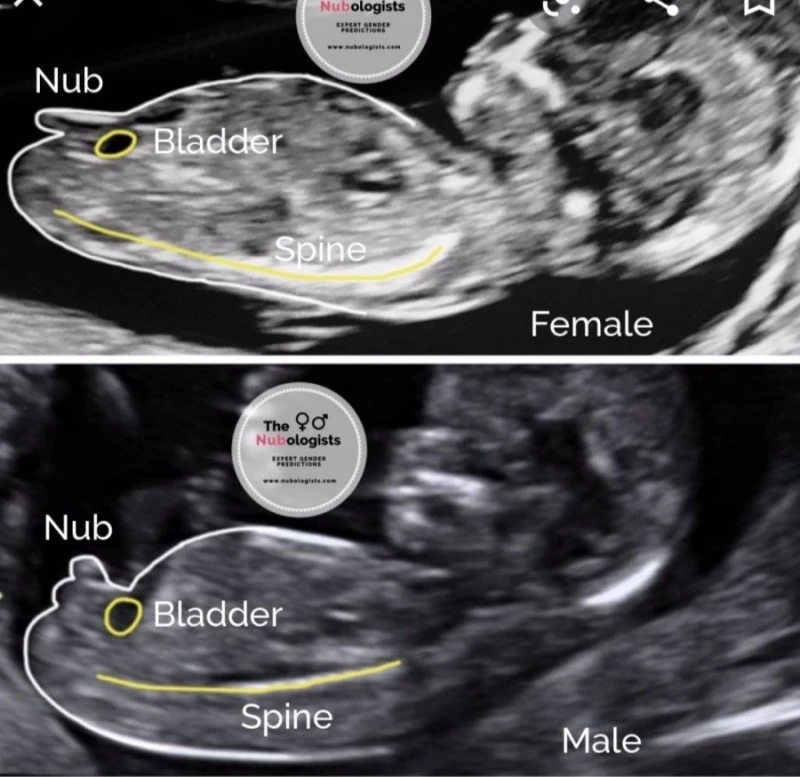

각도 법

가장 믿을만했던 방법이었다.

12주

차 때 아기는 사람의 형상을 갖추고 있는데, 이때 아기의 옆모습을 통해 알 수 있다.

그림에서 알 수 있듯이

아기의 옆모습에서 보이는

성기와 척추의 각도가 평행하면 딸,

성기의 각도가 위로 솟아있으면 아들이다.

물론 아기가 다리를 들고 있다던가,

탯줄을 성기로 착각한다던가 등의 오차가 있다.